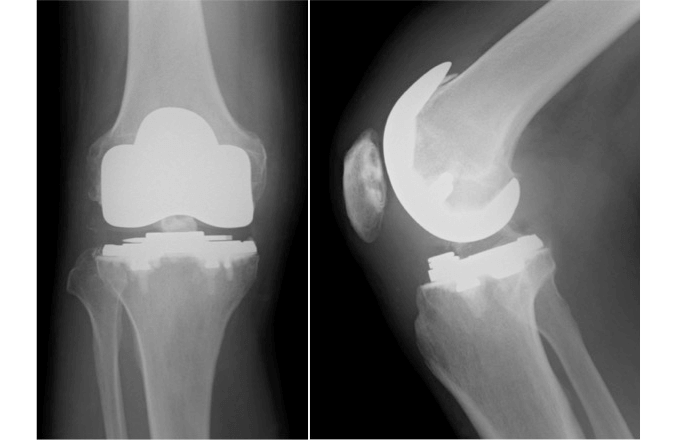

加齢や関節リウマチ、外傷などの原因により高度に障害された関節表面を取り除き、関節部分を金属とポリエチレンに入れ替える手術です。ポリエチレンでできた部分が軟骨の役割を果たし、滑らかに人工関節が動くことができます。

障害された膝関節は人工関節に置換することで痛みが大きく和らぎ、滑らかな動きができるようになり、歩きやすくなります。また、関節の変形も矯正されます。人工膝関節置換術は日常生活の質を高める治療効果の高い手術であると言えます。

以前は膝関節の内側と外側が対称な形状である機種がほとんどでしたが、近年では内側と外側を非対称にして元の膝関節の形状や機能により近くなった機種や、膝の靭帯を全て温存したままで置換できる機種など様々なタイプがあります。患者さんの状態に合わせ、ベストな機種を選び手術を行います。

しかし人工関節置換術における治療の限界もあります。膝関節の可動域は手術前と比べて同じか少し良くなる程度で、劇的な改善は見込めません。また、人工のものであるため、長い間使用し続けることでゆるみや摩耗が生じます。そのため耐用年数は永久というわけにはいかないため、一般には60歳以上が適応年齢となります。さらに耐用年数には個人差があるため、経年的にゆるみがひどくなり再置換術が必要にある場合があります。

従来までの人工膝関節置換術(Total Knee Arthroplasty:TKA)の機械の種類には、上記の後十字靭帯を残したまま手術を行うもの、もしくは後十字靭帯を切除して人工関節で後十字靭帯の機能を代償しようというものでした。

従来のTKAの手術でも良好な成績がたくさん報告されています。しかしながら、TKAの手術後の痛みが残っているという患者さんが約20%もいるという報告もあります。その原因として、TKA後の患者さんの膝は、膝関節内部のもう一つの靭帯の前十字靭帯が切られたままの状態です。そのためTKA後の膝は前十字靭帯が機能していない膝であり、前十字靭帯が機能していないと、術後の膝関節の状態はグラグラと不安定な状態である事が術後の成績が不良な一因として報告されております。

このタイプのTKAは人工関節の機械に前十字靭帯機能を再現し安定性をもたらすと言われています。また、関節面の形状やポリエチレンの厚さを変える事によって、より正常に近い膝関節面と正常膝の動きを再現させるように人工関節がデザインされております。

下の写真は正常膝・従来までのTKA・新しいTKAの側面像を比較したものですが、正常膝の大腿骨と脛骨の位置関係に比べて、従来型のTKAの大腿骨は後方に出っ張っているのがわかるかと思います。このタイプの TKAでは正常膝に近い大腿骨と脛骨の位置関係にあるのがわかると思います。BCS TKAではこのような正常膝に近い前後の位置関係を保つ事や人工関節の機械に工夫を加える事で、前十字靭帯の機能を再現しようとするもので、いい評価に繋がっています。

日本で行われている全人工膝関節置換術(以下TKA)の種類は、後十字靱帯温存型(CR型)が約25%、後十字靱帯置換型(PS型)が約64%、その他が約11%でとなっています。現在よく使用されているインプラントのコンセプトから、そのほとんどは前十字靱帯(以下ACL)を切離する手技が行われています。

TKAは関節リウマチや変形性膝関節症の進行した症例に対しての除痛効果は非常に良好である一方、14-19%が不満足であったという報告があります。また、TKA患者の約1/3に膝の違和感を感じるといった報告もされています。不満足や違和感として、具体的には疼痛残存の他に、音やひっかかり、正常な感覚の消失や望んでいた高い活動ができていないなどが挙げられています。

これらの不満の原因として、前十字靭帯機能の消失が指摘されています。前十字靭帯の主な機能は脛骨の大腿骨に対する前方移動の制御、脛骨回旋の制御、膝伸展時の内外反の制御です。

前十字靭帯の緊張は膝の屈曲角度によって調整され、常に膝の安定性や正常な動作に寄与しており、前十字靭帯は膝の機能維持のために重要であることが分かっています。

現在一般的に行われているTKAでは前十字靭帯は切離されるため、前十字靭帯の機能は損なわれることになります。これが前述のTKA術後の不満足感や違和感に繋がっている可能性が高いのです。

前十字靭帯・後十字靭帯温存型TKAでは、より自然な膝の動きを再現することができると考えられています。 前十字靭帯・後十字靭帯温存型TKAをうけた患者さんは術後の膝がより自然で、安定して音やクリッキングがないと感じたという報告もあり、ACL/PCL温存型TKAは現在のTKAの問題点を解消できる可能性があります。